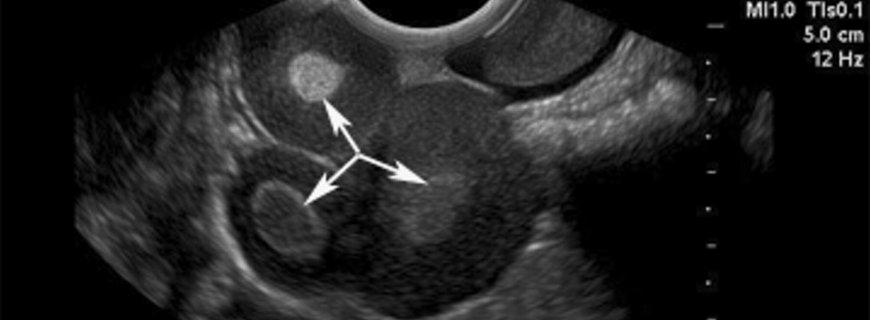

Seröz kistadenomaların birçoğunun özel belirtisi yoktur. Bununla beraber, hastalar kistik kitle ve karında şişlik ile başvurabilirler. Kistleri görmek için ultrasonografi kullanılır. MR iyi huylu kistleri kötü huylulardan ayırmada yardımcı olabilir. Kan CA-125 seviyeleri menopozal yaşta kötü huylu olma olasılığının belirlenmesinde yardımcı olabilir.

Fizyolojik kistlerde tartışıldığının aksine, seröz kistadenoma kendiliğinden ortadan kakmaz. Altı ila sekiz haftada ortadan kalkmayan 5 ila 7 cm’den büyük tüm kitleler için kötü huylu olma olasılığı düşünülmelidir. Ultrasonografi, MR ve kan CA-125 düzeyleri yardımcı olabilecek ameliyat öncesi testlerdir. Bununla beraber bu tümörlerin yaklaşık üçte birine yakınının kötü huylu olma olasılığından dolayı cerrahi patoloji doğru tanı için gereklidir.